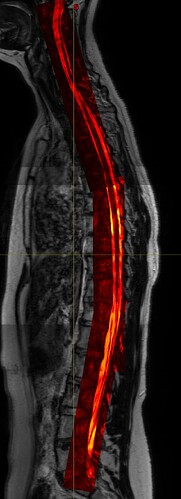

I have acquired some simple T2 images that are easily concatenated as the xyz-axis for all images is the same so I have cervical, thoracic and lumbosacral parts that I can join into 1 spinal cord T2 image. Now I also have some high detail images that only contain the spinal canal and little surrounding tissue with very high contrast within spinal canal but these are also in 3 parts but oriented along the spinal cord. So these 3 images do not have the same orientation which causes them to not be “stitchable”. I already tried getting them to a similar template/orientation but nothing seems to really work. The sct_image either returns only part of the images or just removes parts. While when you visualize them after registering them to the T2 they lie perfectly over eachother, so it is just an orientation problem.

Do you have any ideas on how to get them concatenated? Maybe straighten them separately, then register them to the straightened total T2 and then stitch?